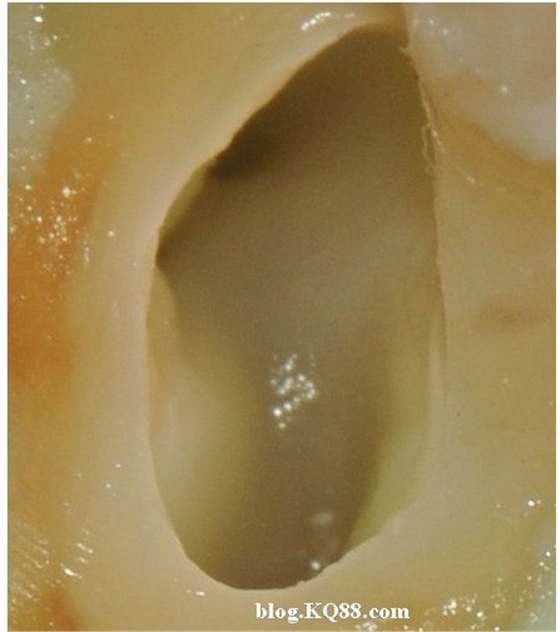

下邊這張圖可以看出氣泡明顯少了,說明次氯酸鈉的溶解速度變慢了。

棉球吸除2%的次氯酸鈉,可以看到牙髓明顯的被溶解掉一部分

換用5%左右的次氯酸鈉很快髓腔內(nèi)的牙髓溶解了

單靠次氯酸鈉作用后的髓腔